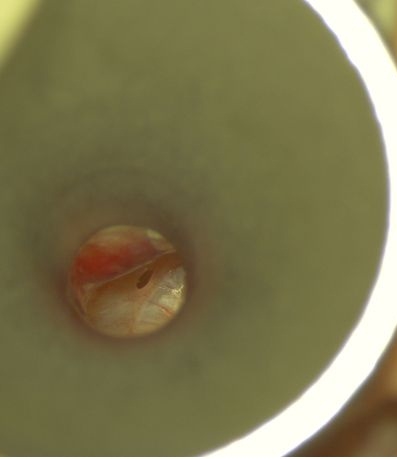

Bogata w płytki i leukocyty fibryna jest stosowana w regeneracji tkanek od ponad 15 lat. Pozytywny wpływ PRF (platelet-rich fibrin) na regenerację tkanek miękkich jest niewątpliwy, bezsporny i częściowo udowodniony w badaniach klinicznych i analizach biochemicznych. Wpływ PRF na regenerację tkanki kostnej jest obserwowany klinicznie, ale nadal niedostatecznie poznany jest mechanizm tego zjawiska.

Platelet- and leukocyte-rich-fibrin has been used in regeneration of tissue for more than 15 years. The positive influence of PRF on the regeneration of soft tissue is undoubtedly, without question and partially proven in clinical studies and biochemical analysis. Influence of PRF on regeneration of bone tissue is observed clinically but the mechanism of this phenomenon is still not sufficiently known.